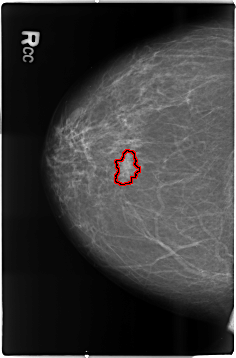

B_3506_1.RIGHT_CC

RIGHT_CC LINES 4648 PIXELS_PER_LINE 3056 BITS_PER_PIXEL 12 RESOLUTION 50 OVERLAY

FILE: B_3506_1.RIGHT_CC.OVERLAY

TOTAL_ABNORMALITIES 1

ABNORMALITY 1

LESION_TYPE MASS SHAPE FOCAL_ASYMMETRIC_DENSITY MARGINS ILL_DEFINED

ASSESSMENT 4

SUBTLETY 3

PATHOLOGY MALIGNANT

TOTAL_OUTLINES 1

BOUNDARY